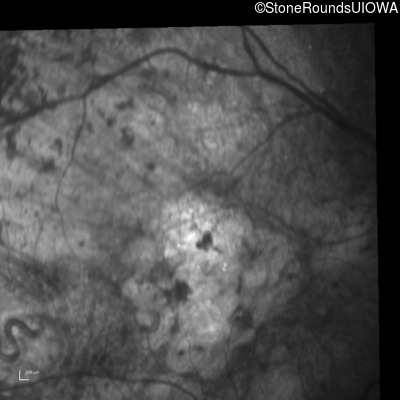

Infrared Fundus Photograph - Right - 1/200 sc

Exemplar